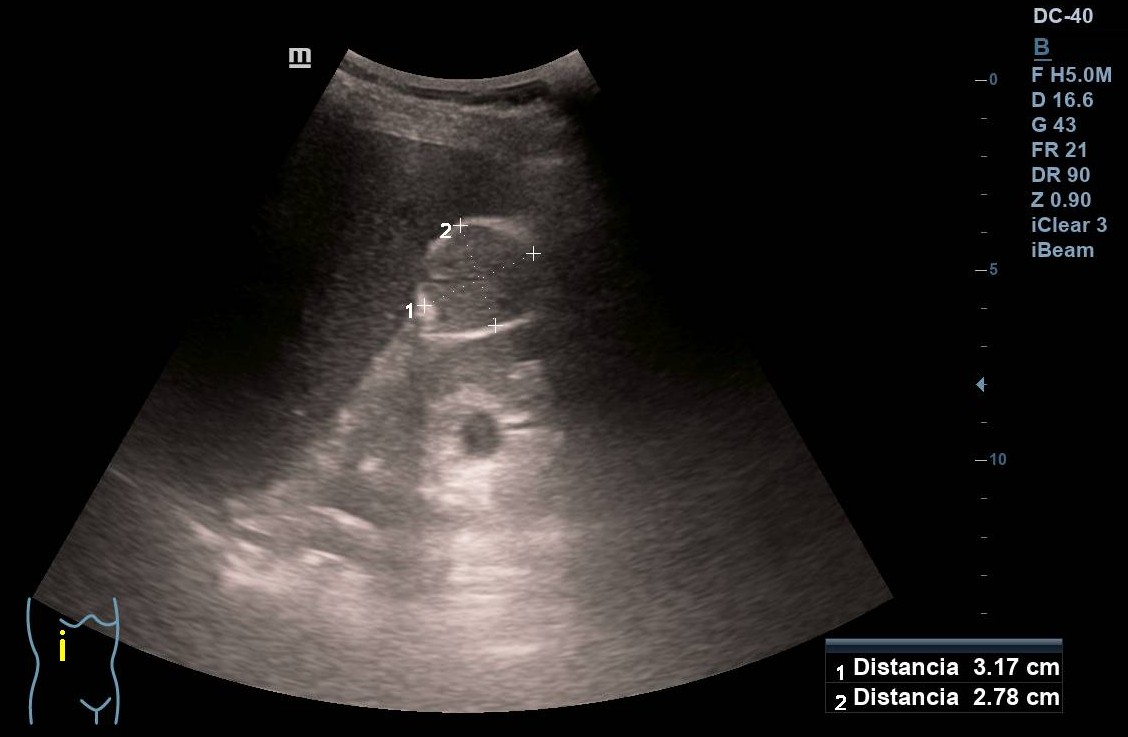

Ante la presencia de hematuria decidimos realizar una ecografía abdominal en el centro de salud. En la vejiga, insuficientemente replecionada, no encontramos lesiones. La próstata también es de tamaño y aspecto normales. En el riñón derecho se observa una masa de unos 3 cm con bordes irregulares.

Tras estos hallazgos se decide derivación preferente a Urología, quien realiza TC que confirma una masa renal de 5 x 3,3 x 3 cm sugestiva de carcinoma renal no metastásico. Además realizan cistoscopia donde se objetiva una lesión papilar vesical de 1 cm, y otra zona eritematosa, sobreelevada y con papilas, en el fondo vesical.